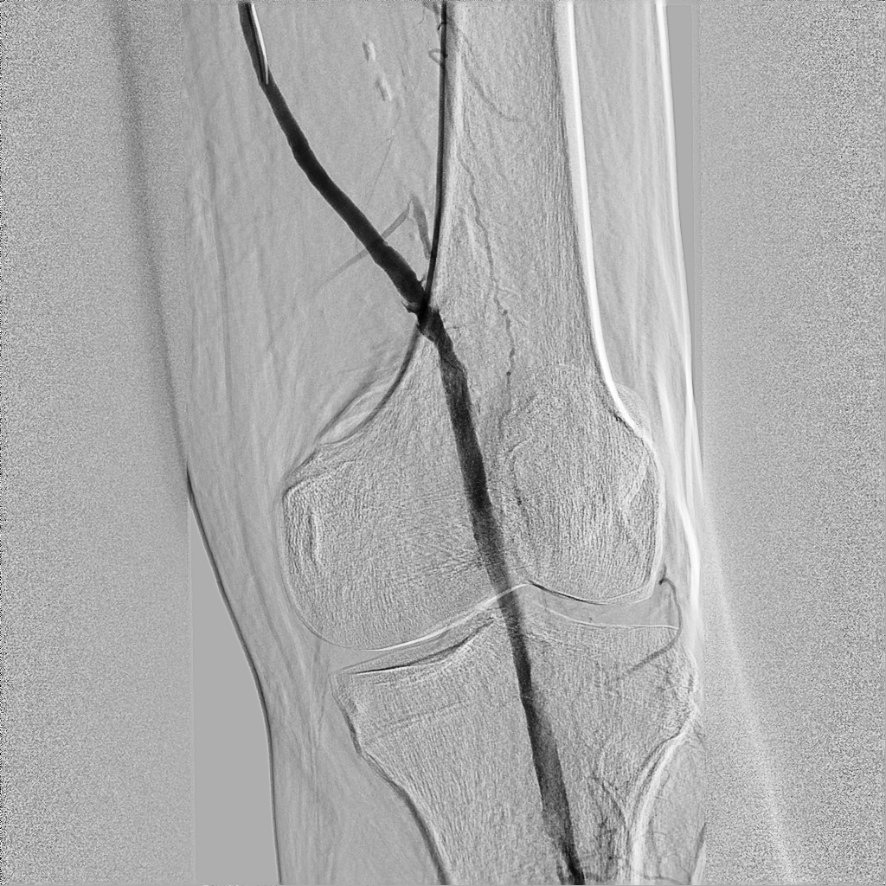

Через две недели пациент снова поступает к нам в стационар. Попытки пройти окклюзию антеградным доступом — через пункцию общей бедренной артерии — не увенчались успехом. Тогда нами была предпринята попытка ретроградной реканализации передней большеберцовой артерии. Под рентген-навигацией была выполнена пункция a.dorsalis pedis на передней поверхности левой стопы. Проводник диаметром 0,014 дюйма проведен через окклюзию передней большеберцовой артерии в подколенную артерию. Баллонным катетером была выполнена продолжительная дилатация передней большеберцовой артерии. На контрольной ангиограмме передняя большеберцовая артерия заполняется полностью до артерий фаланг, плантарная дуга заполняется полностью (рис.3).

![]() Рис.3 Передняя большеберцовая артерия заполняется полностью |